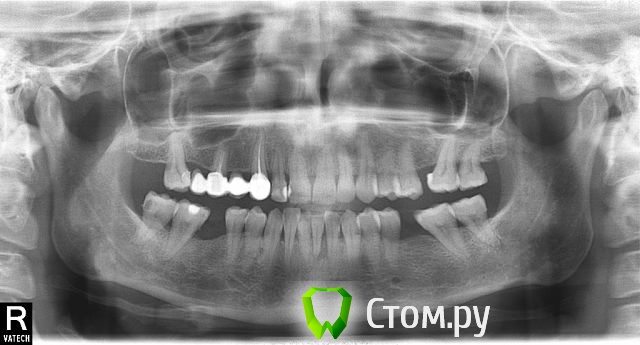

Irina1001 Опубликовано 28 февраля, 2014 Поделиться Опубликовано 28 февраля, 2014 Здравствуйте, уважаемые стоматологи! Посоветуйте, пожалуйста, как поступить.Обратилась к врачу в связи с отстрой болью и отеком нижней десны в области резцов. Диагноз пародонтит и вердикт врачей об удалении всех четырех нижних резцов и имплантации поверг в шок. Зубы абсолютно целые.Прошу высказать ваше мнение, есть ли шанс сохранить зубы, используя другие методы, например, шинирование? Боль сохраняется до сих пор. Снимок прилагаю. Ссылка на комментарий

rivezico Опубликовано 28 февраля, 2014 Поделиться Опубликовано 28 февраля, 2014 (изменено) 31,32 точно под удаление ..другие тоже не оптимистично, к сожалению.. Изменено 28 февраля, 2014 пользователем rivezico 1 Ссылка на комментарий

Bier Опубликовано 1 марта, 2014 Поделиться Опубликовано 1 марта, 2014 согласен, что 32,31 - удаляются 100% 41 под большим вопросом, 42 - возможно оставить. Для имплантации придется кость наращивать. Ссылка на комментарий